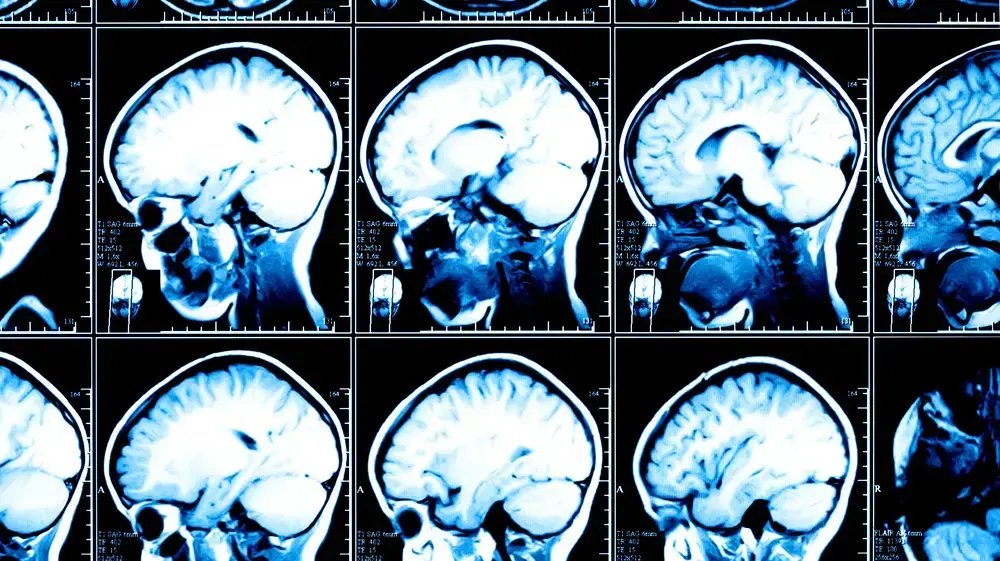

מ שרד הבריאות הודיע על הקמת ועדת בדיקה לתפקוד שירותי בריאות כללית, הגוף הגדול במערכת הבריאות הציבורית בישראל. ההחלטה התקבלה לאחר שורת אירועים...

הדוח של מרכז טאוב חושף כי רמות היוד בשתן של ילדים ומבוגרים בישראל נמוכות משמעותית מהמומלץ על ידי ארגון הבריאות העולמי, מה שמוביל לעיכוב התפתחות תקינה,...